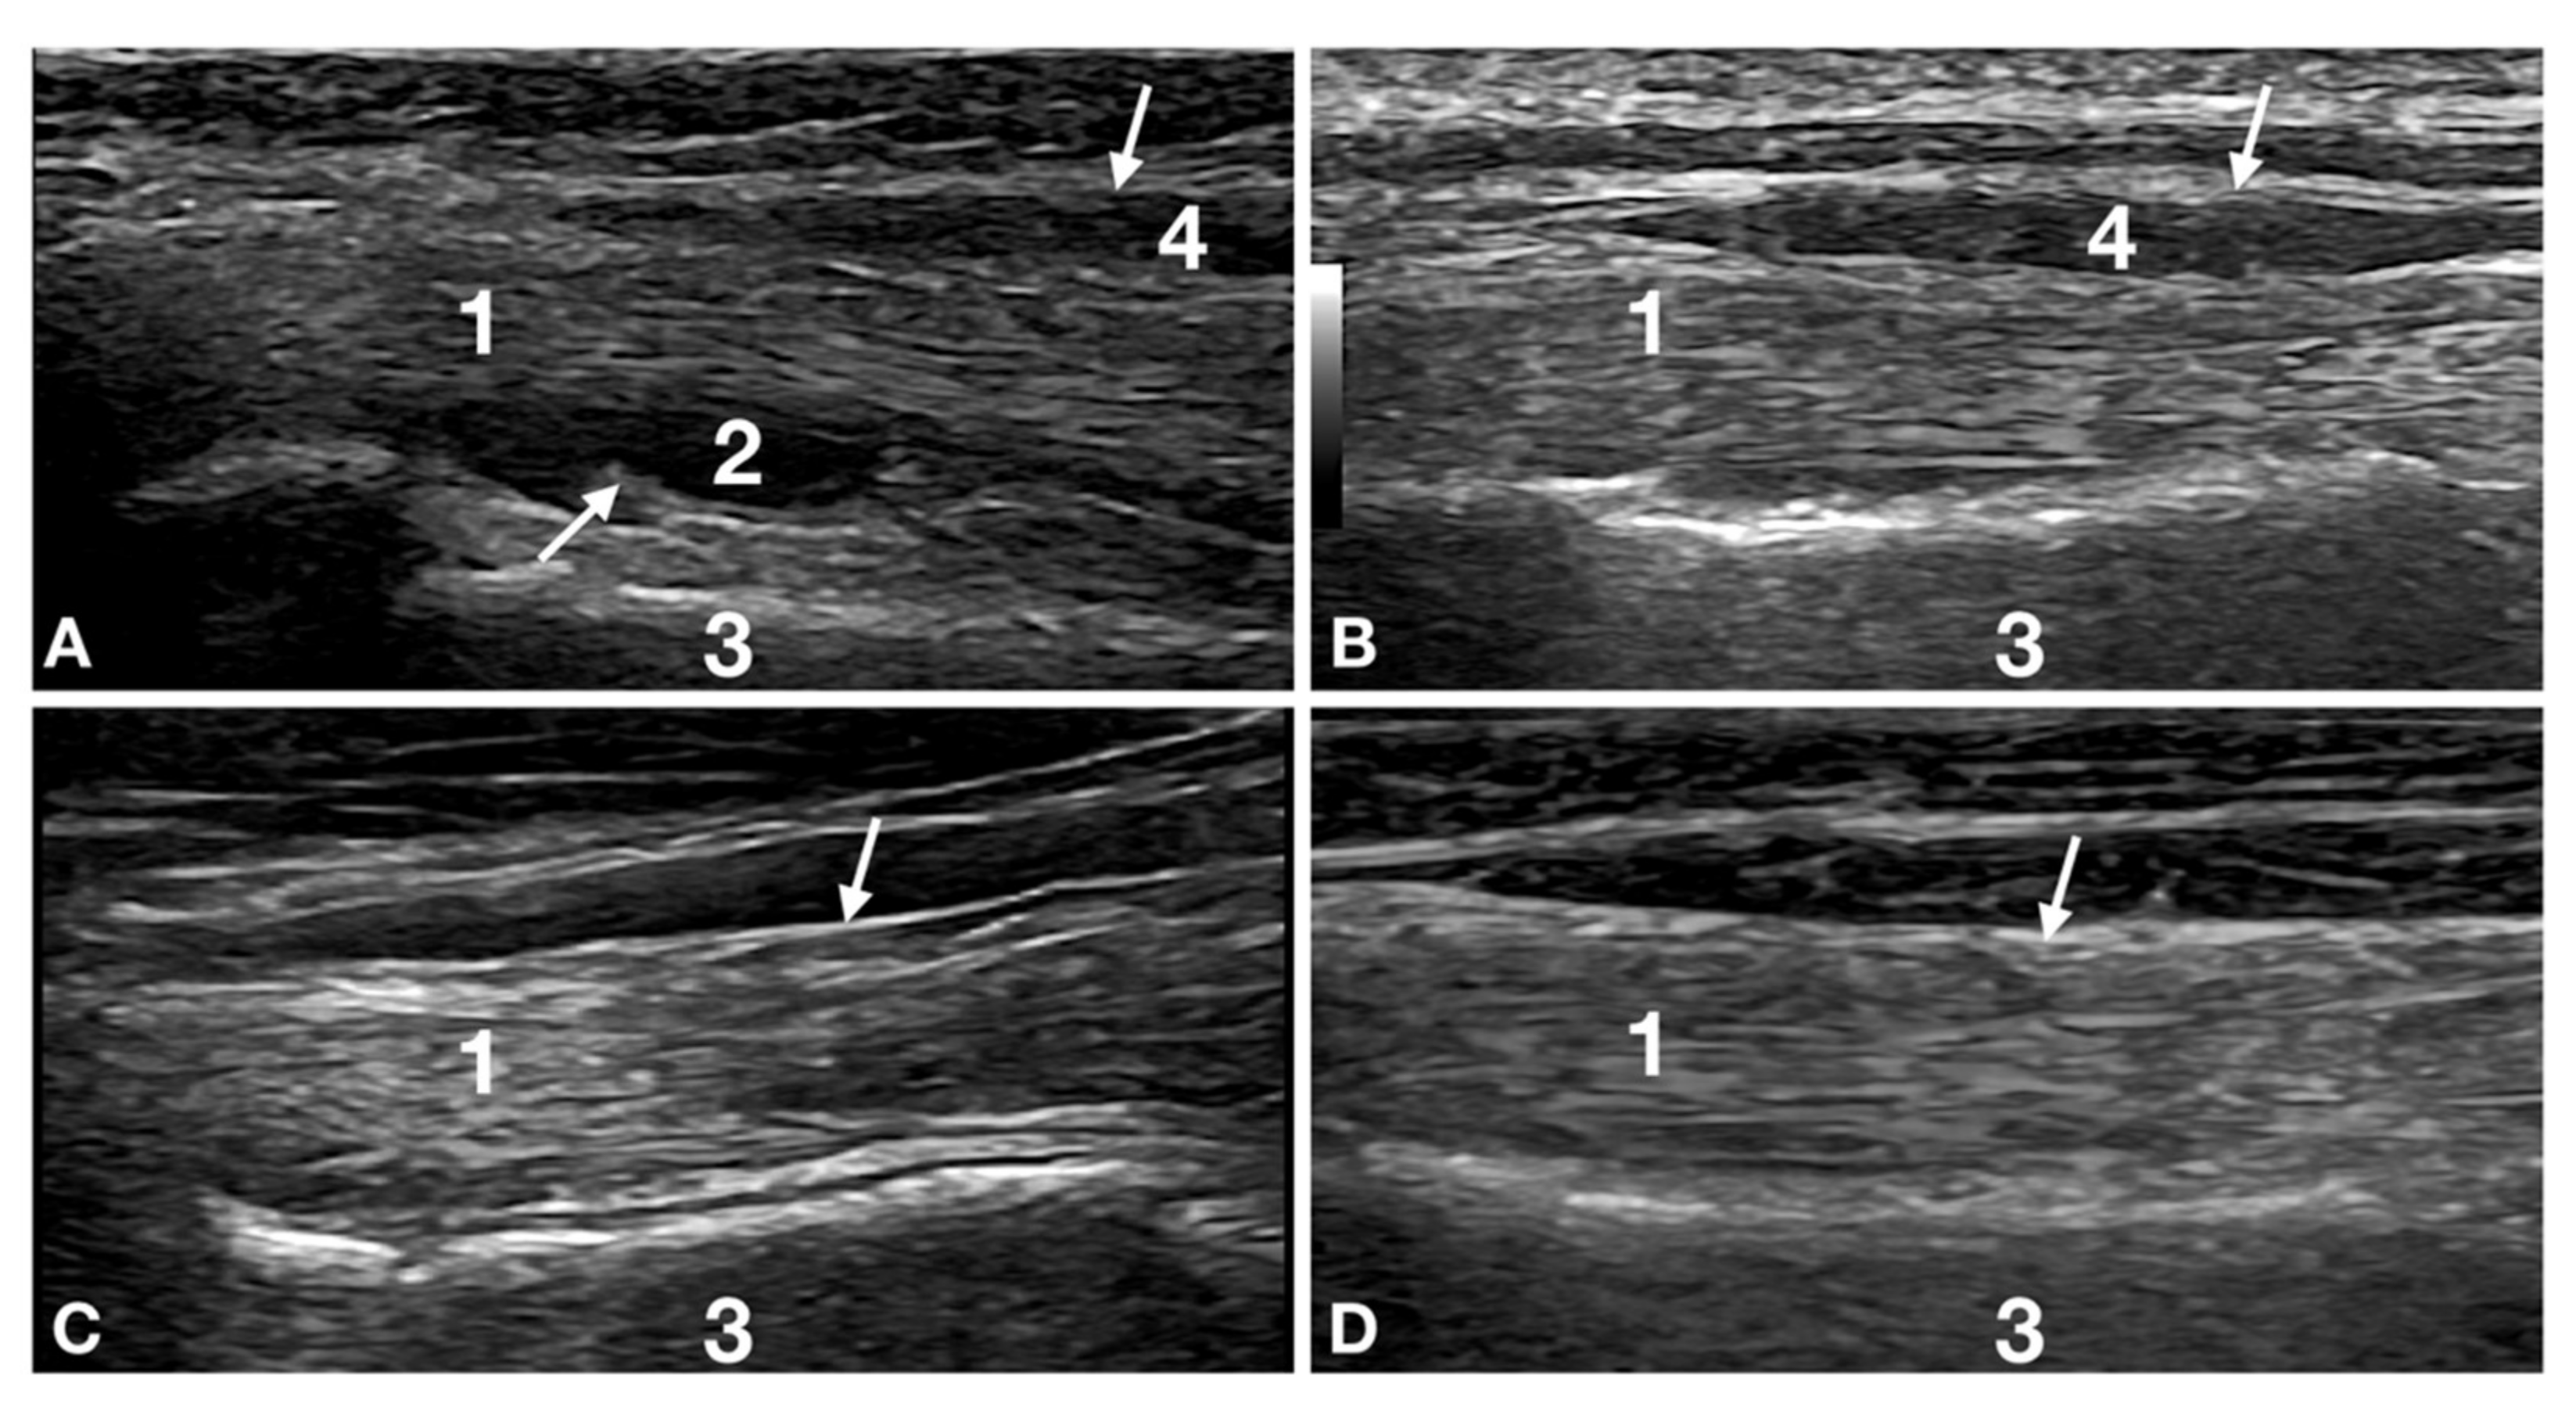

At T0, the most frequent lesion was a reduction in the biceps tendon diameter (24/32; 75%). In general, this finding was associated with fluid accumulation in the biceps tendon sheath (17/32; 53%), shoulder joint effusion (12/32; 37%) and tendon sheath thickening (11/12; 92%) (Figure 1).

Figure 1.

Images of the right biceps tendon distal to the bicipital groove of patient number 12 at Time 0, Time 2, Time 4 and Time 6 are reported. The image shows the progression of healing. (A) Time 0: biceps tendon (1) is not uniform in diameter with a poor fibrillar pattern. The tendon is less echoic with fewer, less defined, thin, hyperechoic lines running along its longitudinal axis. Shoulder effusion (2) is seen between the deeper interface of the tendon and the cranial humeral surface (3). Tendon sheath thickening (arrows) and effusion (4) are evident. (B) Time 2: the biceps tendon (1) is more uniform in diameter thickness but is not the same as the contralateral (not shown but similar to panel d). The fibrillar pattern is mildly increased, and the tendon is more homogeneous and echoic. The shoulder effusion has resolved. The superficial tendon sheath (arrow) is still moderately thickened with mildly reduced effusion (4). (C) Time 4: the biceps tendon (1) is more echoic and is uniform in thickness, with a diameter comparable with the contralateral limb. The fibrillar pattern is better defined but still not identical to the contralateral tendon (compared with panel d). The superficial tendon sheath (arrow) is back to normal for thickness, and there is no visible effusion. (D) Time 6: the biceps tendon (1) is echoic with a fine fibrillar pattern, typical of tendons. The echotexture, echogenicity and thickness are identical to the contralateral limbs (not shown). The superficial tendon sheath (arrow) is back to normal for thickness, and there is no visible effusion. All the lesions are resolved, and no degenerative changes are seen in this patient.

The US follow-up at T4 was carried out in the first week of the maturation part of the remodelling phase of both the tendon and the muscle lesions. All the dogs that remained in the study were considered to be sound; however, 44% of the dogs at this stage (seven graded mild and five graded moderate) had lesions potentially related to lameness, similar to dogs under a high workload. Relative Risk indicated that, four months after the injury, ultrasound was 2.53 times more efficient in identifying a shoulder lesion as compared with only clinical lameness score (CLS). Despite the absence of lameness and the nearly healed lesions, the still not perfectly aligned and packed fibres could have exposed the patients to a potential reinjury as reported in the literature regarding performance in horses and humans. (Figure 1) [34,36]. For this reason, and considering the highly demanding training necessary for competition, it was decided, based on the ultrasound results, to delay the RTP of the patients for an additional six weeks. At the same time, the patient started a gradually increasing workload, intended as training and reinforcement of the mostly healed lesions and the shoulder apparatus in general.